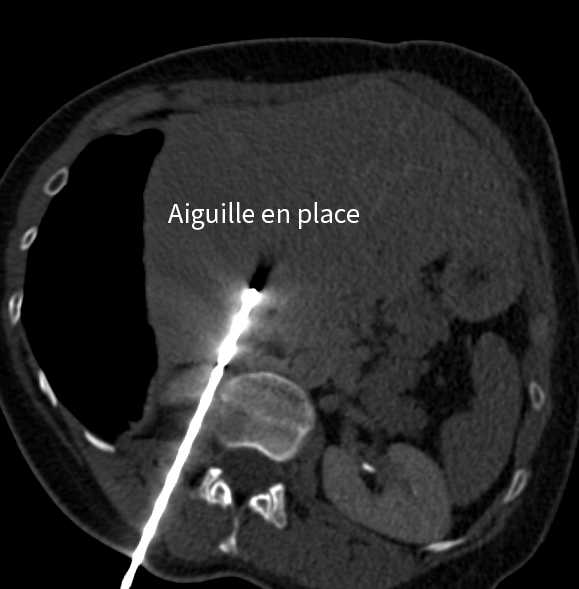

Le geste consiste à :

• repérer précisément la lésion grâce à l’imagerie,

• insérer une ou plusieurs aiguilles,

Traitement hépatique par micro-ondes

Dans un second temps, la métastase hépatique est traitée par thermoablation micro-ondes, avec protection des organes voisins grâce à une technique d’hydrodissection.

En images

Images du traitement des organes (poumon et foie) avant, pendant et après le traitement.